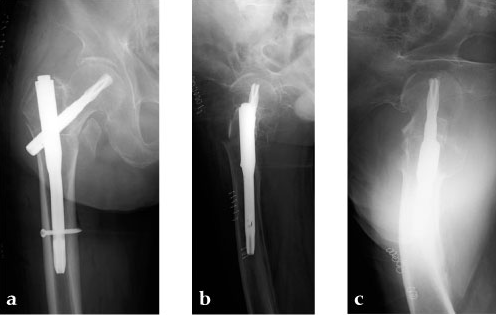

Case 4: 77-year-old male.

Case provided by Takeshi Sawaguchi, Toyama, JP

78-year-old female.